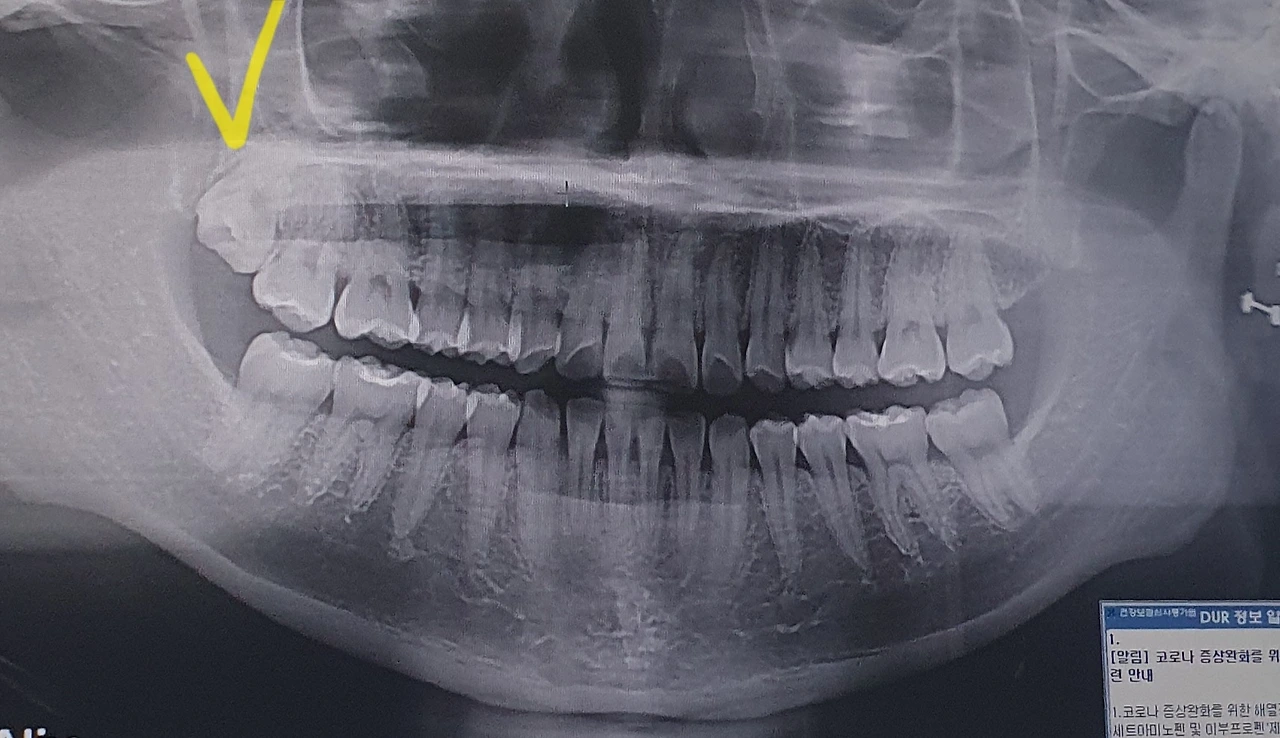

사진만 봐도 '군식구'라는 말이 더할 나위 없이 어울린다.

드디어, 의사 선생님이 후- 하고 숨을 내뱉으시며 아주 잘 뽑혔다고 말씀하셨다. 일어나서 내쫓은 군식구 사랑니를 구경하니, 아주 걸뱅이 같은 녀석이 좁은 내 턱에 비집고 들어가 있었다는 것을 알았다. 크기도 내가 가진 이빨들 중에 가장 컸고, 다리도 3개나 되는 데다가 그 다리를 베베 꼬고 있는 형태였다. 의사 선생님이 왜 나사 돌리듯 빼셨는지, 이제야 이해가 갔다. 어이가 없기도 하고, 신기하기도 해서 이빨을 달라고 해서 집에 데려왔다. 비롯 내쫓은 군식구지만, 대단한 녀석이었구나. 지금 이틀 정도가 지났는데 빈자리가 크게 느껴진다. 아주 욱신거린다.